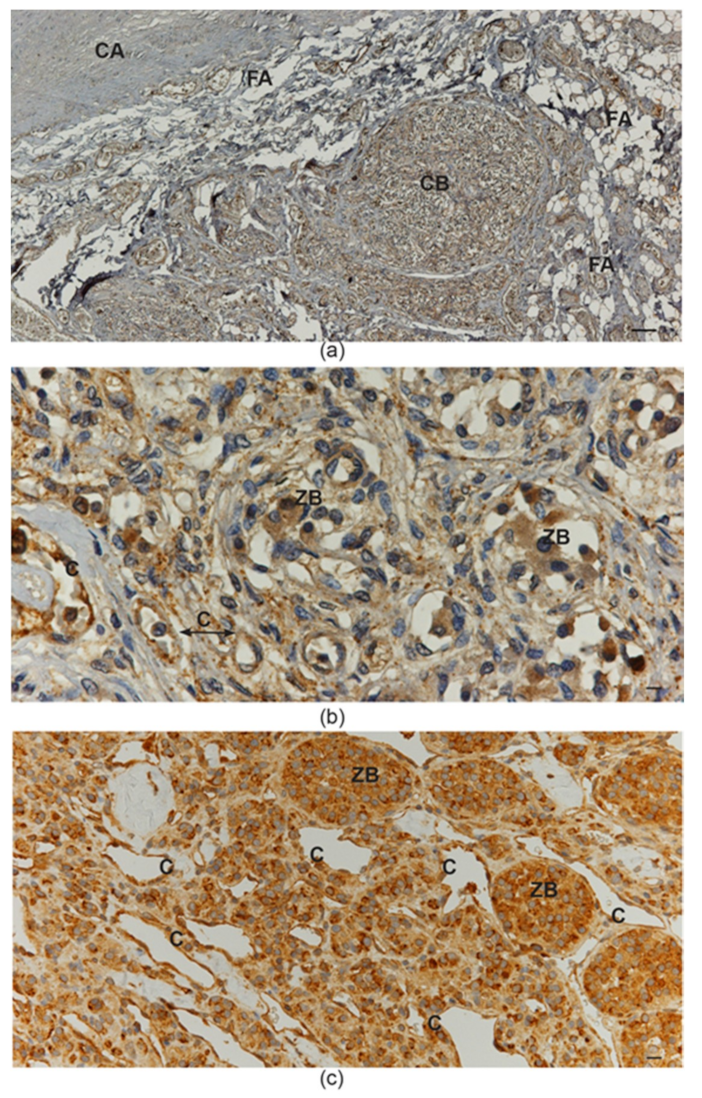

4. Ultrastructural and Immunomorphological Relationships Between the Vascular and Neural Compartments of Head and Neck Paragangliomas

5. Our Approach to the Study of Genes and Pathways Shared Among Head and Neck Paragangliomas

6. Constitutive Notch Signaling in Head and Neck Paraganglioma